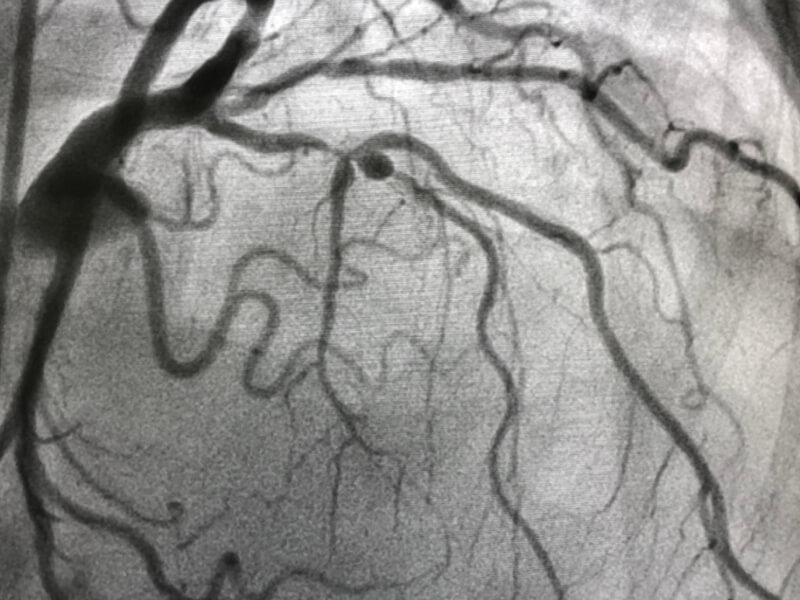

BHF-funded research has helped understand if doctors should unblock all blocked arteries or just the main culprit, when treating heart attacks.